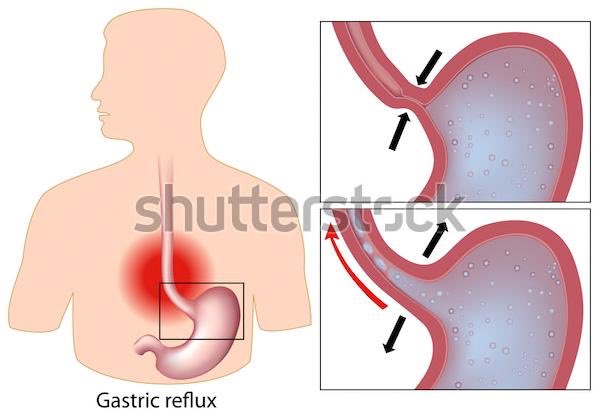

متى تزور الطبيب ؟ إذا كنت تعاني من ألم في الصدر، خاصة إذا كنت تشعر أيضًا بضيق في التنفس أو ألم في الفك أو الذراع